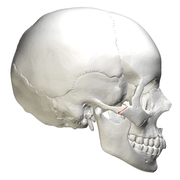

| Side view of the skull. (Zygomaticotemporal suture is suture between zygomatic bone, at left in white, and temporal bone, at center in pink.) |